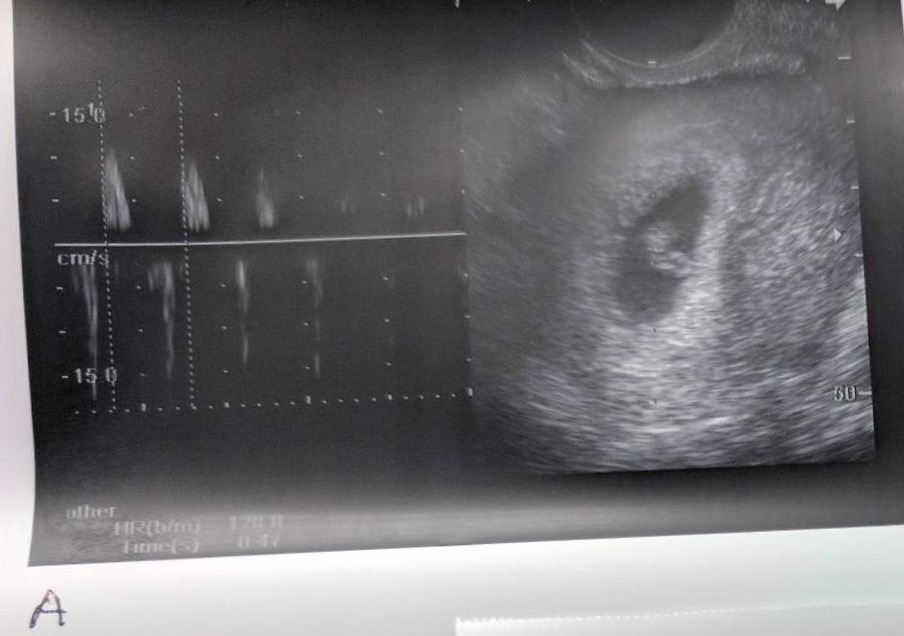

Can't tell its a baby right now but the head is on the left (black space is part of the brain. Yolk sac is the oval on the right.